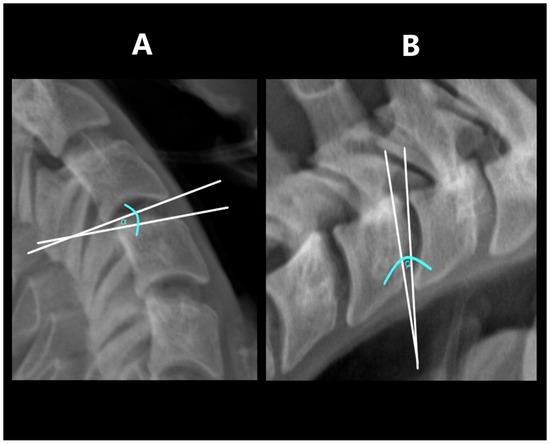

2.5. Cobb Angle

The Cobb angle was determined as the angle between two straight lines drawn tangentially to the lower edge of the C2 and C7 (Figure 1) [9,10]. Where the lower edge of C7 was not visible in the examination, due to the patient’s inability to take the required position, a C2–C6 substitute measurement with comparable diagnostic value was made [11]. Where the lower edge of the C6 vertebra was also unavailable, the measurements were abandoned (a total of 13 examinations in 11 patients). After taking measurements in functional projections, the sum of the obtained values was also calculated.

Figure 1. Cobb’s angle measurement: (A)—in flexion, (B)—in extension.